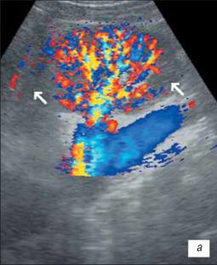

УЗІ нирки при запальних змінах в режимі ЦДК

а – інтраренальний судинний малюнок нирки збережений, кортикальный кровотік визначається у всіх відділах паренхіми;

б – збіднення судинного малюнка;

в – швидкісні показники в гирлі ниркової артерії в межах вікової норми: Vps – 83,7 см/с; Ved – 34,1 см/с; RI – 0,63; PI – 0,96.

На розгорненій картині УЗІ з ЦДК характеризується нерівністю, нечіткістю, деформацією контура нирки, який місцями може не простежуватися; нирка іноді місцями погано диференціюється від навколишніх тканин, що утрудняє визначення її розмірів; візуалізуються дрібні, неправильної форми втягнення контура, розподілені або по всьому контуру, або в якомусь фрагменті нирки; визначається нечіткість кортико-медуллярной диференціювання; є виражені дифузні зміни паренхіми нирки з помірним нерівномірним підвищенням її эхогенності; дилатація чашечно-мискової системи; фрагментарне стоншування паренхіми нирки з компенсаторним потовщенням або збереженням товщини інших її ділянок помірне збіднення інтраренального судинного малюнка, найбільш виражене в місцях деформації і втягнення контура нирки; зниження швидкісних характеристик артеріального кровотоку (мал. 3).